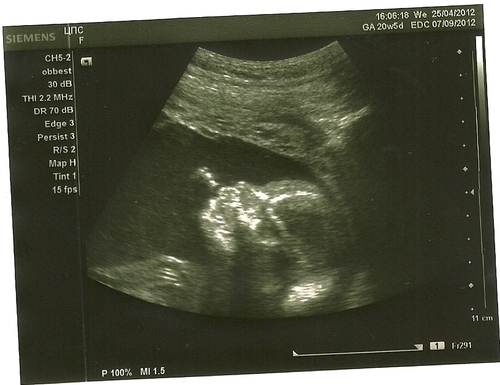

20 й неделе беременности

20 й неделе беременности 118 фотографий